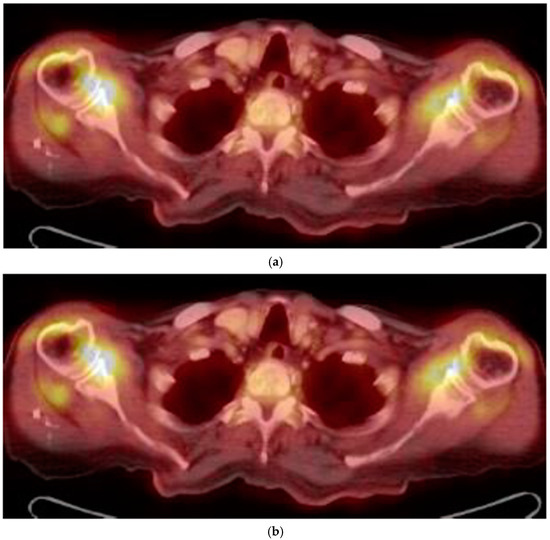

- US and 18-FDG PET/CT evaluations might increase diagnostic rates of ESR and CRP negative PMR.

- Yuge, S.; Nakatani, K.; Yoshino, K.; Koyama, T. Diagnosing polymyalgia rheumatica on 18-F-FDG PET/CT: Typical uptake patterns. Ann. Nucl. Med. 2018. [Google Scholar] [CrossRef] [PubMed]